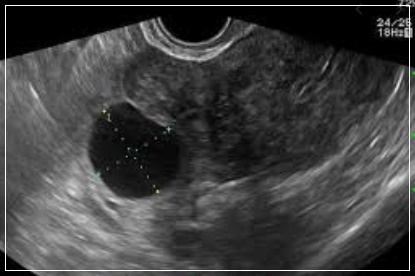

자궁,난소 등의 이상 소견을 확인하는 여성생식기 초음파 검사는 여성에서 흔히 발생하는 질환인 자궁근종, 난소 낭종 등을 진단하기 위한 기본적인 검사방법임에도 불구하고 그 동안 4대 중증질환(암·심장·뇌혈관·희귀난치)에 한해 제한적으로 건강보험이 적용됐 왔습니다.

특히나 자궁근종, 자궁내막증, 난소 낭종 등은 여성에서 흔히 발생하는 질환임에도 불구하고 건강보험이 적용되지 않았다. 전체 진료의 약 93%가 비급여로서 환자가 검사비 전액을 부담했습니다. 연간 비급여 규모는 약 3,300억 원으로 건강보험 적용 확대가 크게 요구되는 분야였습니다.

이번 건강보험 적용 확대로 자궁근종 등 여성생식기 질환자의 초음파 검사 의료비 부담이 2분의 1에서 4분의 1수준까지 경감됩니다. 가장 일반적으로 여성생식기 질환의 진단 및 경과관찰에 시행하는 초음파 검사의 비급여 관행 가격은 의료기관 종류별로 평균 4만7400원(의원)에서 13만7600원(상급종합병원)으로 현재 이를 환자가 전액 부담하고 있습니다.